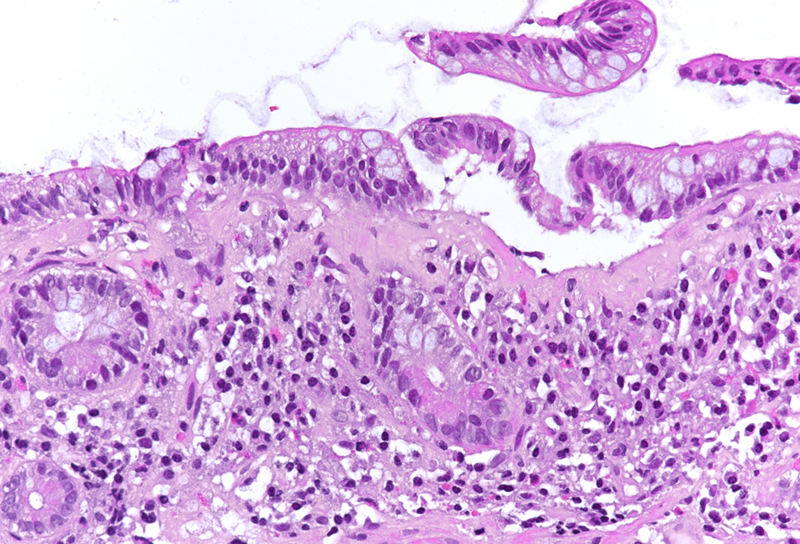

Colon biopsies from a 66-year-old male with chronic diarrhoea.

Collagenous colitis with giant cells.

Histologic examination showed irregularly flattened large-bowel mucosa with diffusely increased inflammation in the lamina propria, the inflammatory infiltrate consisting of plasma cells, lymphocytes and eosinophils. In all biopsies, a prominent, irregularly thickened (> 10 µm) collagen band was observed under the surface epithelium (Panel A), which could be highlighted by modified trichrome staining (CAB; Panel B). The surface epithelium was detached and showed degenerative changes. No crypt architectural distortion or metaplastic changes were observed, and no signs of active inflammation were present. Interestingly, several multinucleated giant cells were seen in the lamina propria close to the thickened subepithelial collagen band (Panels C-D).